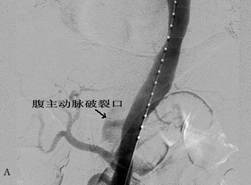

图2 患者男,57岁,胸腹痛7小时急诊入院,诊断为主动脉夹层(Standford B型),入院1周后行主动脉夹层腔内修复术,术后10天临床治愈出院。A为治疗前造影,B为覆膜支架修复破裂口后。